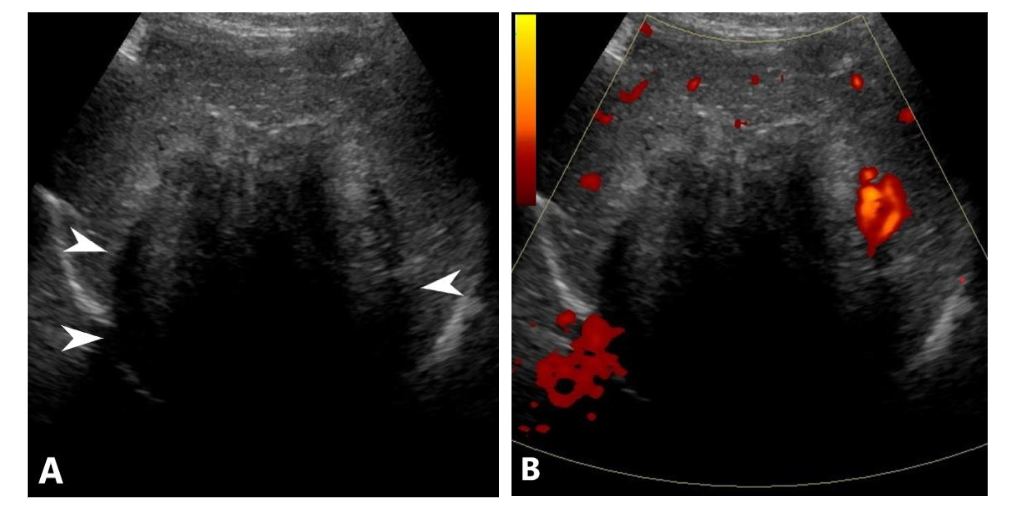

A 17-year-old female, previously healthy, presented with abdominal pain and pruritus for several months. She noticed jaundice in her eyes for the last two weeks but denied acholic stools. These symptoms were associated with a 10-pound weight loss and fatigue. She was not on any steroids or oral contraceptive pills. Initial lab data showed a total bilirubin of 4.7 mg/dL (0.0-1.2), alkaline phosphatase of 390 unit/L (40-130), AST of 101 unit/L (10-45), and ALT of 162 unit/L (7-45). Abdominal ultrasound (Figure 1) showed a large lobulated mixed echogenicity mass centered on the right hepatic lobe containing several hypoechoic components with posterior acoustic shadowing without a discernible central scar. Color Doppler showed scanty peripheral vascularity without significant internal vascularity. The spleen was moderate to markedly enlarged with a craniocaudal dimension of approximately 19 cm. Upon further laboratory evaluation, CA 19-9 was 68.8 units/mL (Nl: up to 35) with normal serum alpha-fetoprotein and beta-HCG. Abdominal MRI (Figure 2) showed a large, predominantly T1/T2 hypointense mass with delayed progressive enhancement (Figure 3). There was no signal drop throughout the lesion on out-of-phase images to suggest a fat component. DWI and ADC mapping demonstrated a predominantly hypointense signal (T2 blackout). No central scar was appreciated within the hepatic lesion. Mild, regular dilation of peripheral intrahepatic biliary ducts was also identified due to the mass effect on the biliary system. Splenomegaly and collateral vessels were present. There was no tumoral invasion or thrombosis of the inferior vena cava.

Ultrasonography (US) Findings:

The tumor appears hypoechoic with marked posterior acoustic shadowing, despite the absence of internal calcification, indicating a dense collagenous composition.

Pediatric sclerosing epithelioid fibrosarcoma in the liver is extremely rare with no described imaging appearance in the current literature. In this presented case, significant posterior acoustic shadowing of the hypoechoic component of the hepatic mass on ultrasonography corresponding to low signal T2 appearance, and progressive delayed enhancement on MRI are imaging clues that can help radiologists to arrive a narrow differential consideration and differentiate this tumor from other hepatic malignancies.